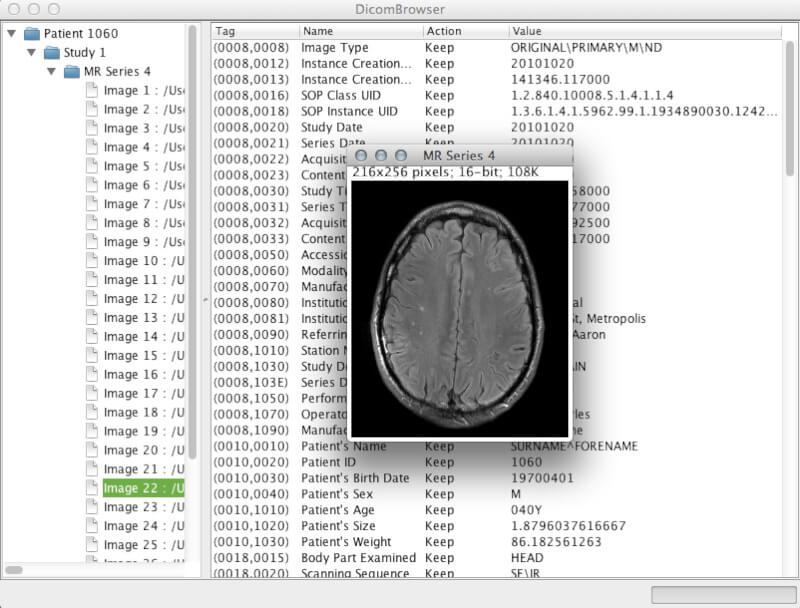

2. DicomBrowser

DicomBrowser is an open source Java-based DICOM metadata inspector and modifier app. It was developed by the Neuroinformatics Research Group of Washington University to be excellent at batch anonymizations.

It is cross-platform, can simultaneously load thousands of images, and also features a command line interface to the anonymization script engine.